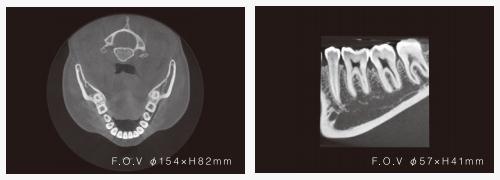

そうぜん歯科クリニックではRF社製 NAOMI-CTを導入しています。

頭部の周りを360°回転して撮影するフルスキャンCTで、神経や歯の根っこの周りまで詳細に観察することができます。

従来の二次元のパノラマレントゲンと比べ、より正確な診査・診断ができるため、治療計画が立てやすくなります。